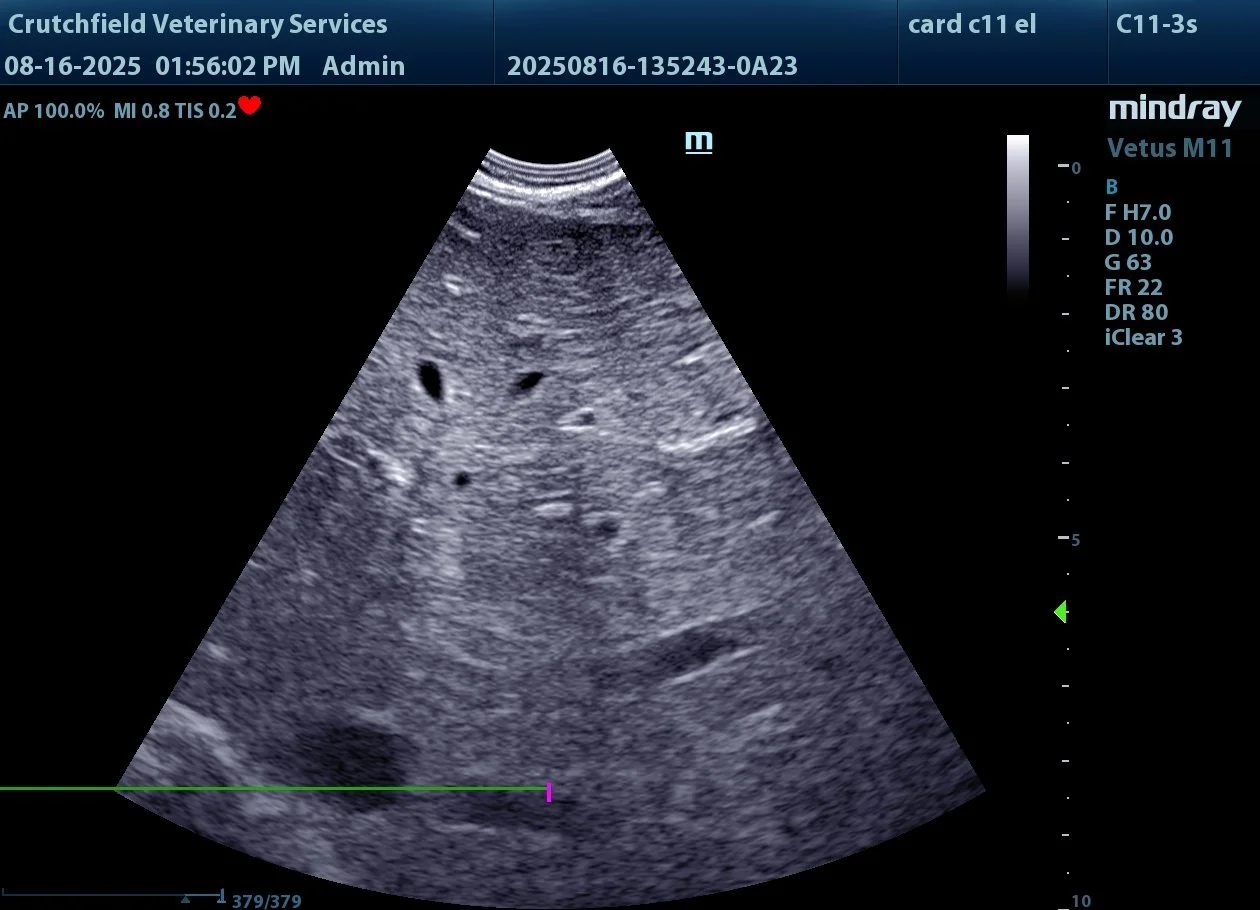

Dr. Crutchfield performs ultrasound exams on dogs and cats by appointment only. Please call, text or email to schedule your pet’s ultrasound.